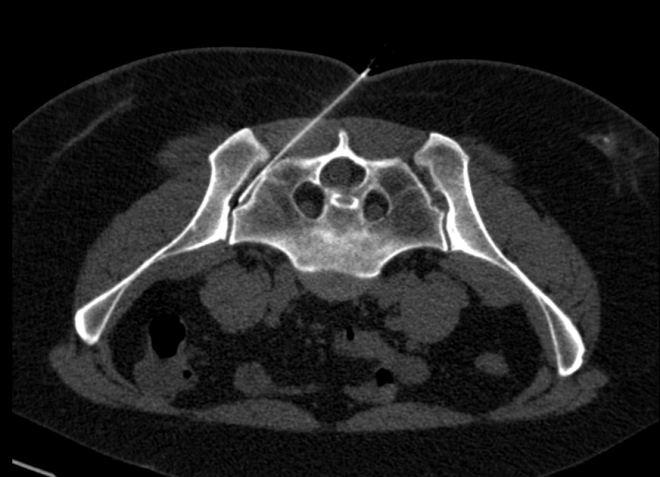

Poté následovala punkce pravého SI skloubení pod CT kontrolou (obr.2) s podáním malého množství kontrastní látky, dále bylo podáno RF (74 MBq Rhenium 186 sulhide susp.), následně aplikován depotní kortikoid a anestetikum.

/ Obr.2.: Aplikace RF pod CT kontrolou - pravé SI skloubení. /